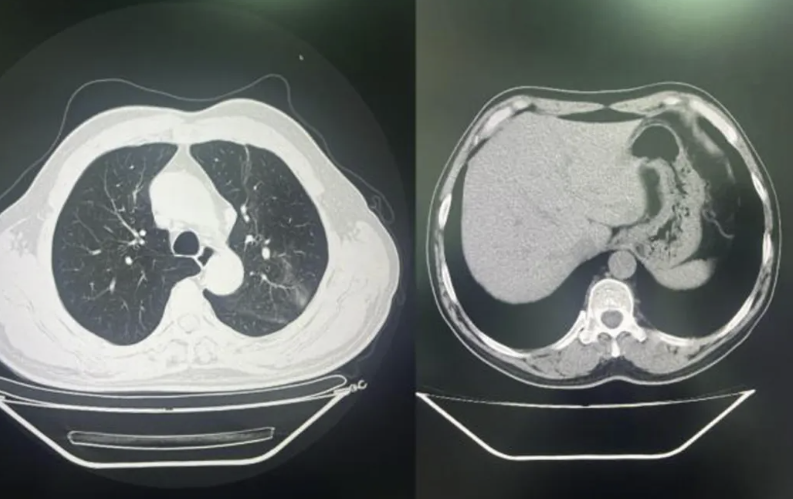

4.胸部CT:左肺上叶炎症,纵膈淋巴结肿大,肝脏右叶低密度影(见图1)。

图1:左肺上叶炎症,纵膈淋巴结肿大,肝脏右叶低密度影